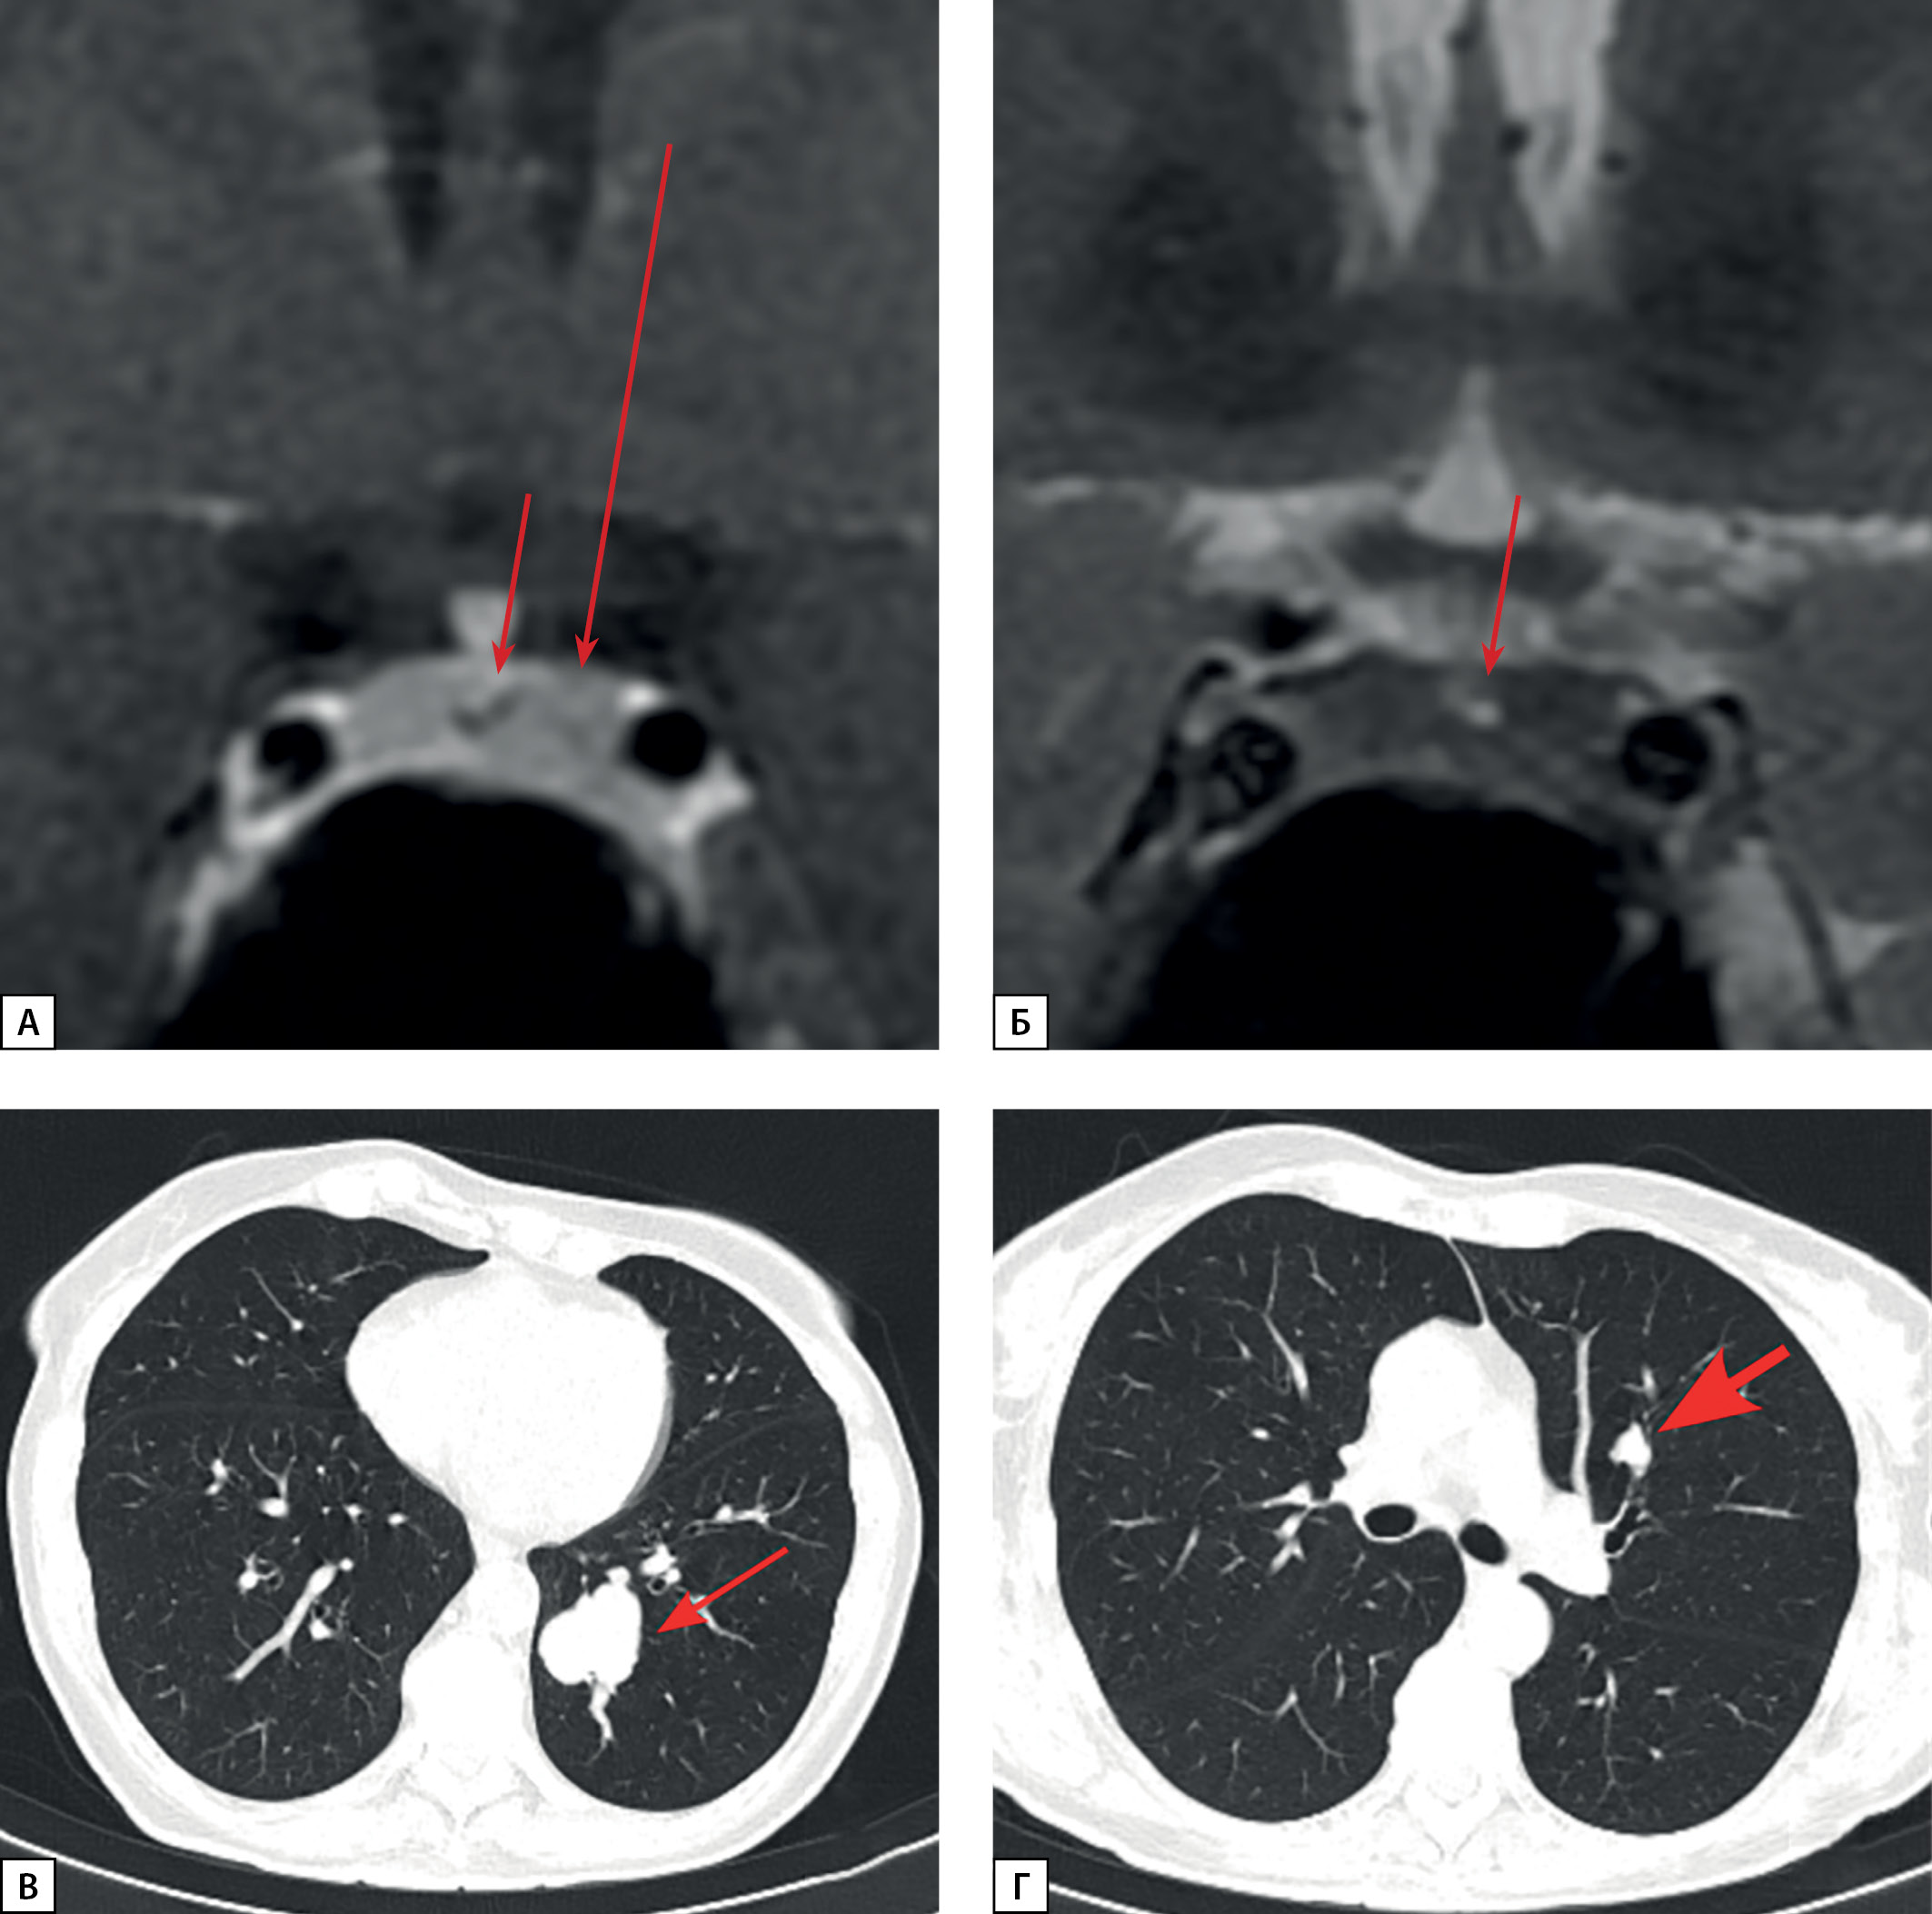

Figure 7: Patient S.N.A. MRI and CT scans.

A: pre-surgery pituitary MRI coronal T1 WI contrast. A pituitary macroadenoma (see arrow); B: post-surgery pituitary MRI coronal T1 WI contrast. A pituitary macroadenoma (see arrow), decreased in size; C: lung MSCT; pulmonary mode, arterial phase, axial projection. A neuroendocrine tumour in S4 of the left lung (see arrow).

A female patient S.N.A., born in 1978, was first admitted to Endocrinology Research Centre at the age of 41 with complaints of headache, back pain, joint pain, facial swelling, hair loss, weight gain, menstrual cycle irregularities (delays). From the age of 37 she began to notice enlargement of the feet, hands and nose, fingertip numbness, and menstrual cycle delays. At the age of 40, she was seen by an endocrinologist at her local medical practice, and acromegaly was suspected during examination. GH level was 8.29 ng/ml (0.5–7), but no IGF-1 data were available at that time. Contrast brain MRI revealed a 25×30×33 mm pituitary macroadenoma with endo-, supra-, infra-, and latero- (into the left cavernous sinus, Knosp Grade 3) sellar growth. It compressed the optic nerve chiasm (Fig. 7a). Iron deficiency anaemia due to heavy menstruation associated with uterine myoma was also detected at that time. At the age of 41 the patient underwent transnasal transsphenoidal adenomectomy at her local clinic. Histological examination found a “large-cell pituitary adenoma”. After the surgery, secondary hypothyroidism developed, but acromegaly remission was not achieved, thus the patient was referred to Endocrinology Research Centre. Before admission, due to complaints of persistent cough, the patient underwent a chest MSCT, which revealed a 15×12 mm lesion in the upper lobe of the left lung, which the oncologist considered benign on the basis of CT phenotype.

At the age of 44, the patient was readmitted to Endocrinology Research Centre for a follow-up examination. At the time of admission, she was receiving long-acting octreotide 40 mg once in 28 days (the dose was increased by her local physician due to the lack of IGF-1 level normalisation). During examination, the absence of acromegaly remission was confirmed: IGF1 was at 300.8 ng/ml (51–271). Contrast brain MRI found a cystic-solid lesion of heterogeneous structure in the sella turcica, in the sphenoid sinus (spreading to the posterior labyrinth). The lesion was protruding from anterior pituitary and unevenly absorbing contrast and had the same size: vertical – 18 mm, transverse – 21 mm, anteroposterior – 25 mm, without any changes vs. the previous examination. Given a lung lesion in the history, a contrast chest MSCT was performed: in the left S4 lung parenchyma a perivascular solid lesion 15×12×19 mm was seen with smooth and slightly bulging contours, moderately absorbing contrast agent (native/ arterial/ venous/ deferred phases: 13/ 15/ 69/ 79 Hounsfield Units). Conclusion: the lesion was most consistent with NET (Figure 7c). A S4–5 bisegmentectomy on the left side with groups 3, 5, 7, 9 lymphodissection was performed. Morphological examination detected a dense, homogeneous pale yellow 1.6×1.5×1.3 cm tumour nodule located within the lung lobe tissue. Microscopically, the tumour nodule was a dense cellular formation with scanty, slightly eosinophilic, vaguely contoured cell cytoplasm and small oval uniform nuclei. The cells formed solid-alveolar structures; no foci of necrosis were found. There were three mitoses in 50 fields of view at ×400 magnification. The tumour involved the bronchus wall, grew under the epithelium of its mucous membrane and narrowed the bronchus lumen. The nodule had a clear border with the surrounding pulmonary tissue, without a visible pseudocapsule. A IHC study revealed tumour cells to have diffuse expression of chromogranin A (clone DAK-A3, DAKO), Ki-67 (clone SP6, Cell Marque) – nuclear expression in less than 1% of cells. Conclusion: typical carcinoid of the left lung, Grade 1, with a lesion of the upper lobe subsegmental bronchus wall, without invasive elements in the resection margins and without metastases in seven regional lymph nodes.

Given the findings, ectopic acromegaly was suspected. IHC examination revealed diffuse GHRH expression, which confirmed ectopic acromegaly diagnosis (Figure 9).